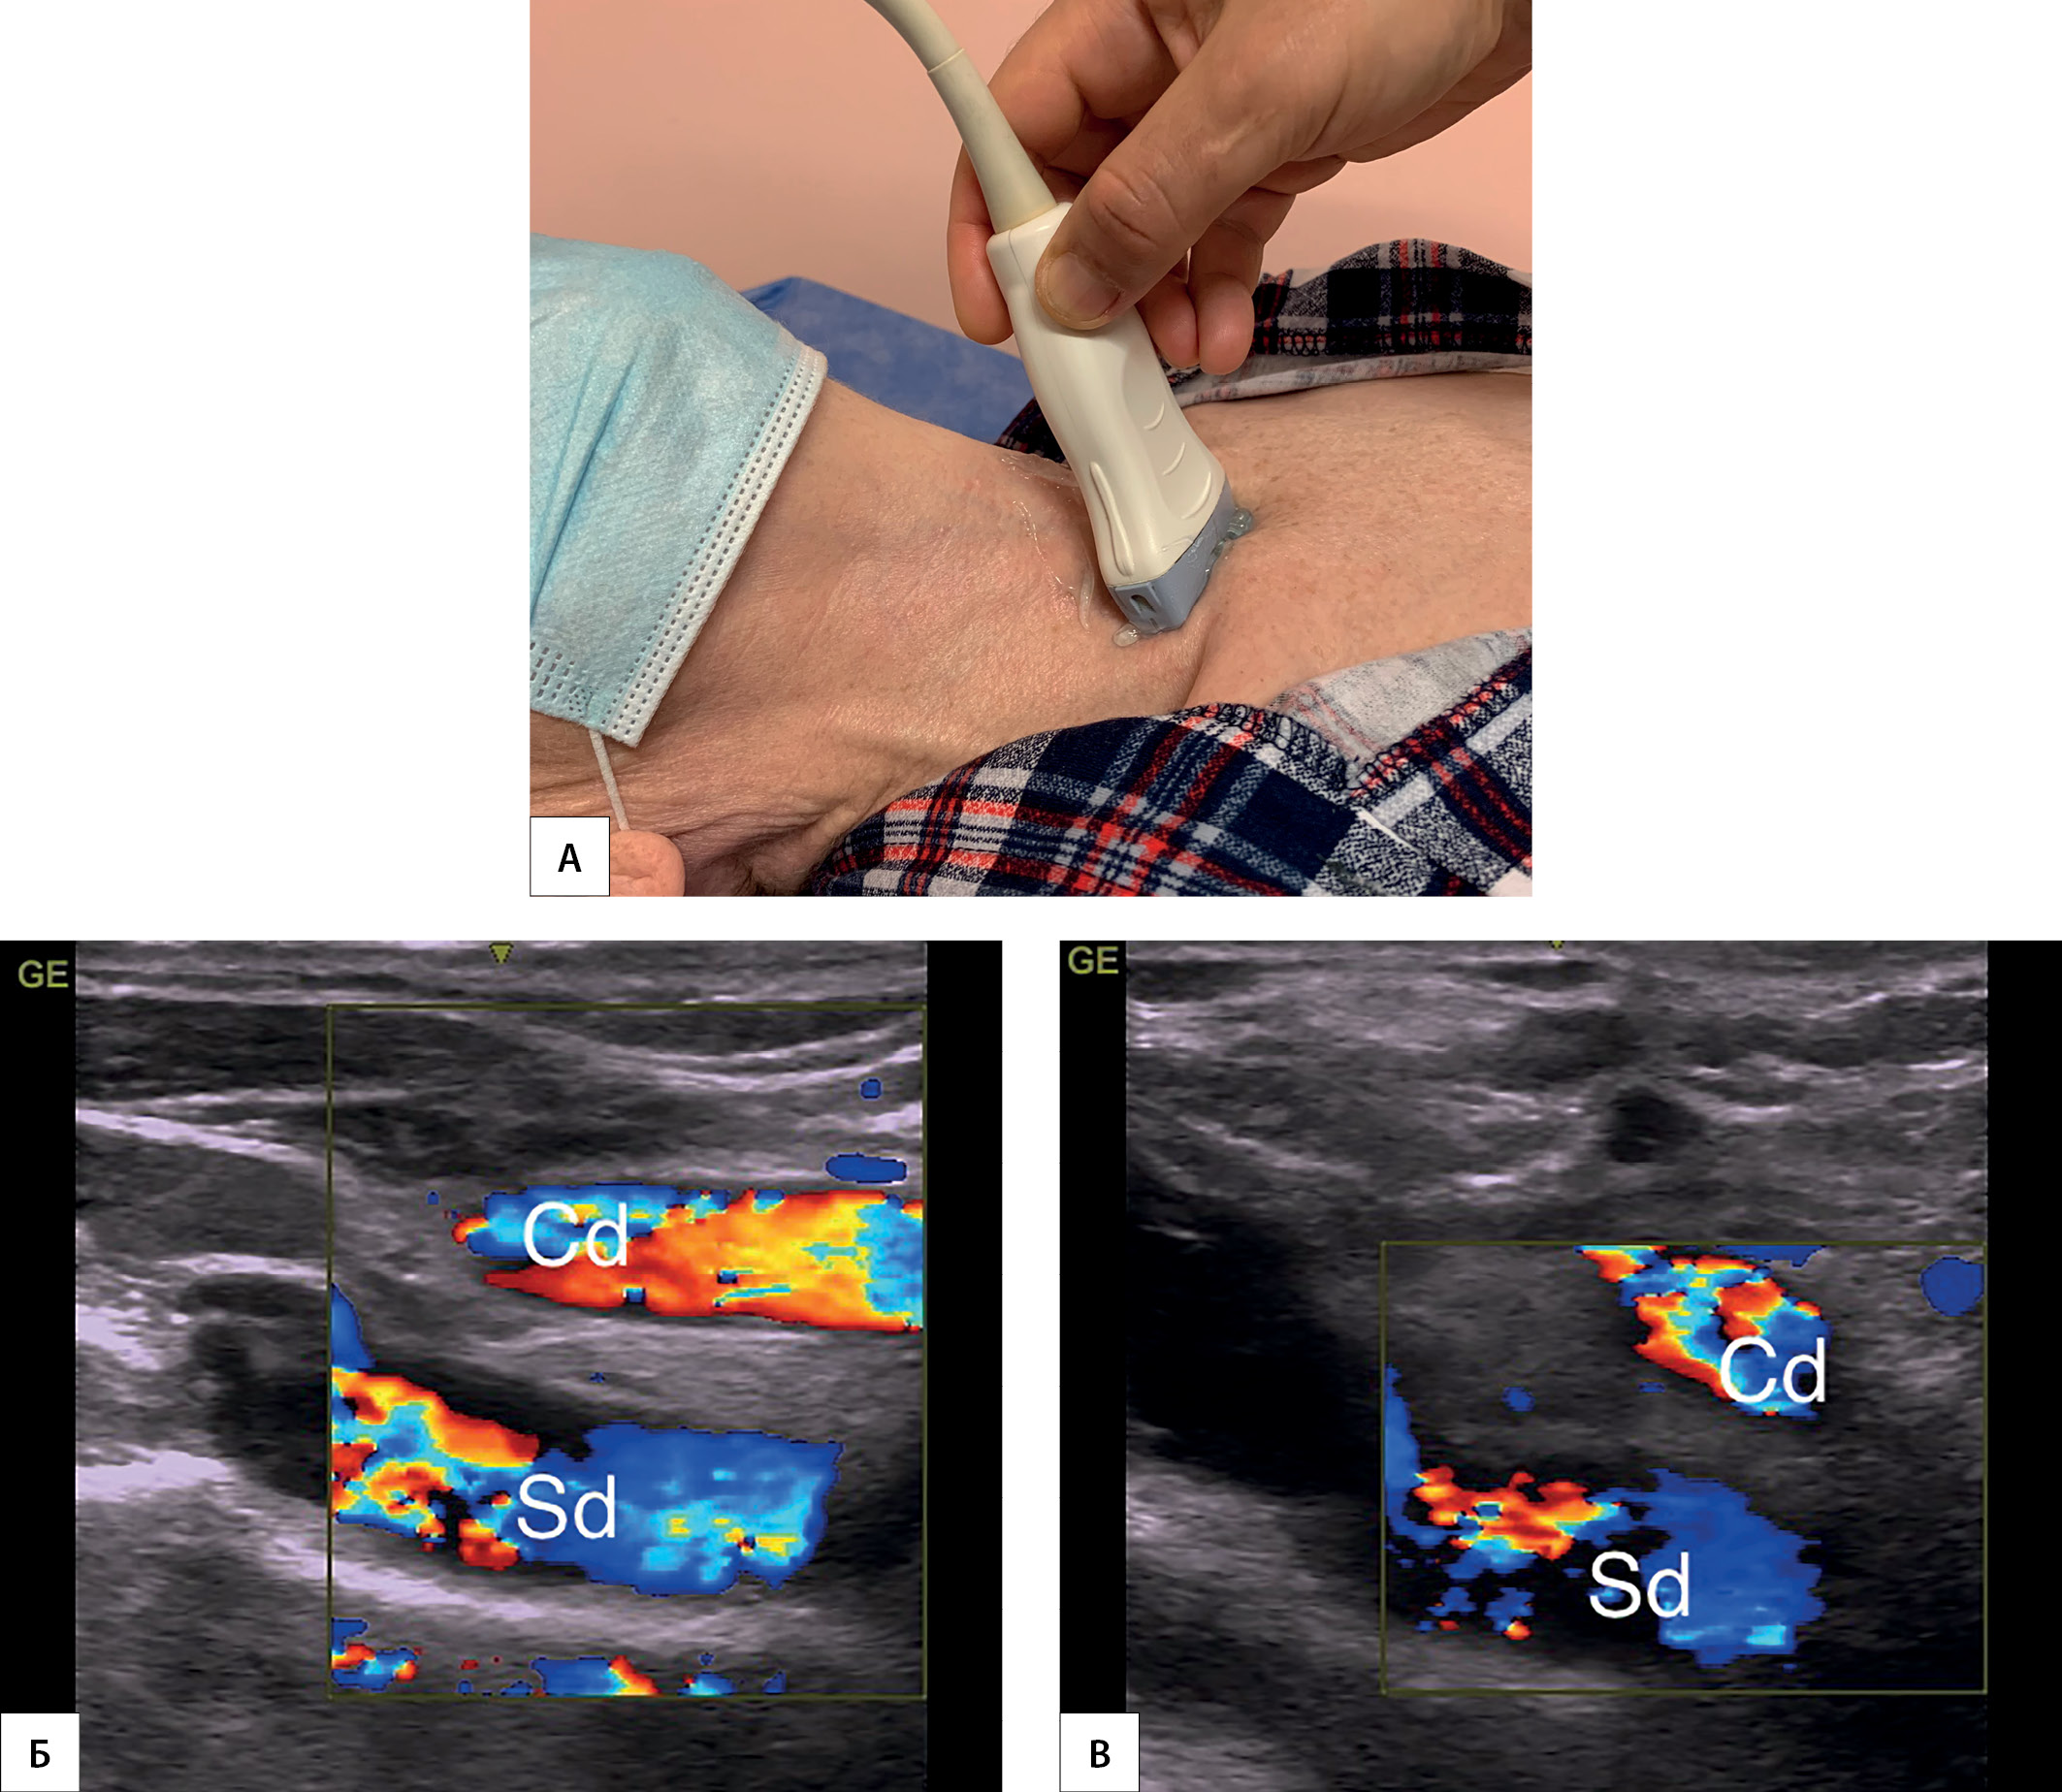

2. Рисунок 2. Эхографические признаки AL (AL-признак).

Тема

Тип Исследовательские инструменты

Посмотреть (754KB)